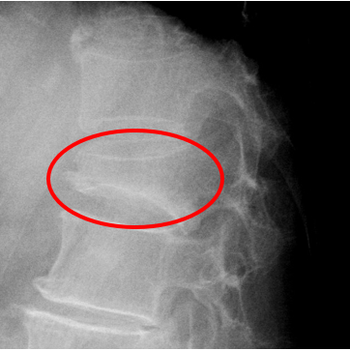

亀背変形

圧迫骨折のレントゲン

がんの骨転移

圧迫骨折であれば、早期に治療を始めることで亀背変形を最小限に